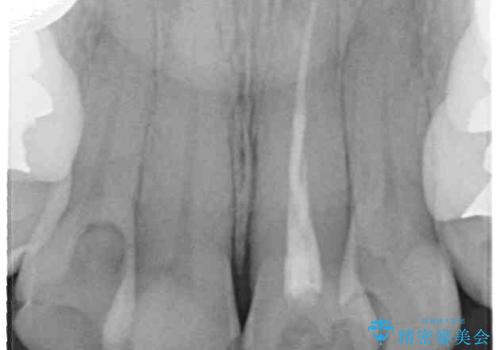

- 歯列全体が内側に倒れ込んでいることと、口元の突出感を気にして来院された患者様です。

上下ともに歯列が狭窄しており、前方に突出している状態でした。

歯が重なるような叢生も認められたため、上下左右の第一小臼歯4本を抜歯して、口元が引っ込むように治療を行うこととしました。